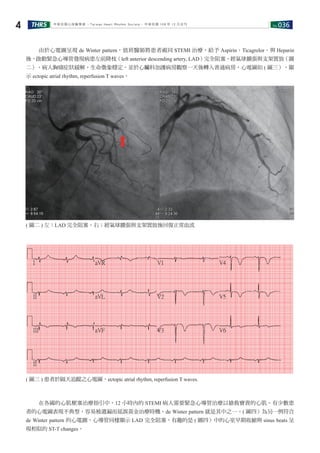

由於心電圖呈現 de Winter pattern,值班醫師將患者視同 STEMI 治療,給予 Aspirin、Ticagrelor、與 Heparin

後,啟動緊急心導管發現病患左前降枝(left anterior descending artery, LAD)完全阻塞,經氣球擴張與支架置放(圖

二),病人胸痛症狀緩解,生命徵象穩定,並於心臟科加護病房觀察一天後轉入普通病房,心電圖如 ( 圖三),顯

示 ectopic atrial rhythm, reperfusion T waves。

( 圖二 ) 左:LAD 完全阻塞。右:經氣球擴張與支架置放後回復正常血流

( 圖三 ) 患者於隔天追蹤之心電圖,ectopic atrial rhythm, reperfusion T waves.